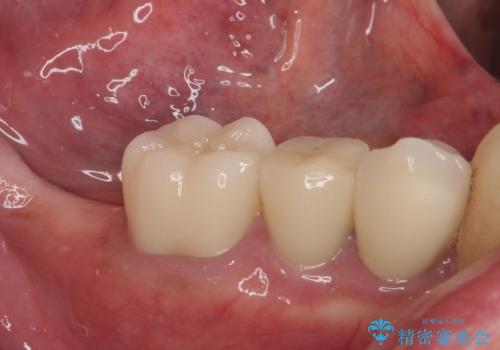

破折してしまった奥歯 抜歯即時埋入で短期間インプラント治療

- 奥歯に装着していたクラウンが外れてしまったとのことで来院された患者様です。

診察したところ、歯根に破折線が確認され抜歯が必要な状態でした。

歯肉や歯槽骨の状態は良好であったため、抜歯即時埋入インプラントによる補綴治療を行うこととしました。

抜歯、インプラント埋入、仮歯の装着を1度に行うことができ、治療終了までわずか3か月で終えることができました。